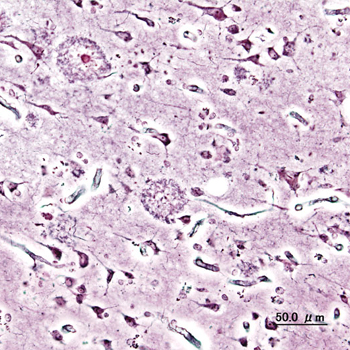

Logran evitar pérdidas de memoria en el alzhéimer

Un equipo de investigadores del <a href="https://www.csic.es/es" title="Centro Superior de Investigaciones Científicas" alt="Centro Superior de Investigaciones Científicas" target="_blank">Centro Superior de Investigaciones Científicas</a> (CSIC) ha descubierto un mecanismo para evitar la pérdida de memoria en la enfermedad de Alzheimer, por medio de un estudio con modelos de ratón que permite orientar acerca de posibles vías de intervención terapéutica.